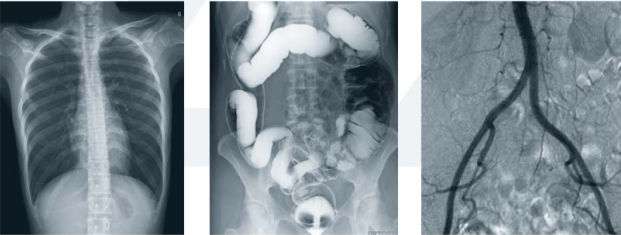

胃腸造影離不開現(xiàn)代化的數(shù)字化胃腸顯影方式(一類運用常規(guī)胃腸機達(dá)到檢查目的;另一類則運用新推出的動態(tài)DR達(dá)到檢查目的),它是一種能通過造影診斷用來檢查胃腸道疾病的X線檢查設(shè)備,是檢查各種潰瘍、腫瘤及異物等疾病的主要檢查方法之一。

隨著動態(tài)DR的這股旋風(fēng)的盛起,部分胃腸機廠家也開始大勢宣傳其胃腸設(shè)備同樣具備動態(tài)功能。不過從市場的綜合反饋來看,雖然胃腸機在影像診斷上相比以前的醫(yī)療設(shè)備都有了較大的進(jìn)步,但和真正意義上的動態(tài)DR依舊有一定的差距。

為什么目前市場上有很多客戶意愿選擇動態(tài)DR這么一款多功能的產(chǎn)品作為替代胃腸機的一類放射設(shè)備頭一個選擇,有哪些優(yōu)勢呢?常規(guī)胃腸機和動態(tài)DR對比優(yōu)劣勢如下:

動態(tài)DR胃腸造影檢查和消化內(nèi)鏡相輔相成,在胃腸道疾病的診斷方面具有其他檢查方法無可比擬的優(yōu)勢。僅在考慮特異性、適用性、普遍性的胃腸檢查上不難發(fā)現(xiàn),動態(tài)DR胃腸造影檢查略有優(yōu)勢。特別是疑難病例上,全面分析胃腸大概狀況,離不開造影的有效應(yīng)用。

同時, 動態(tài)DR的應(yīng)用實現(xiàn)了狀態(tài)和功能同時記錄觀察,既可留下大量的資料,又拓寬了檢查范圍,對臨床工作者的使用慣性和操作都有不可替代的地位。